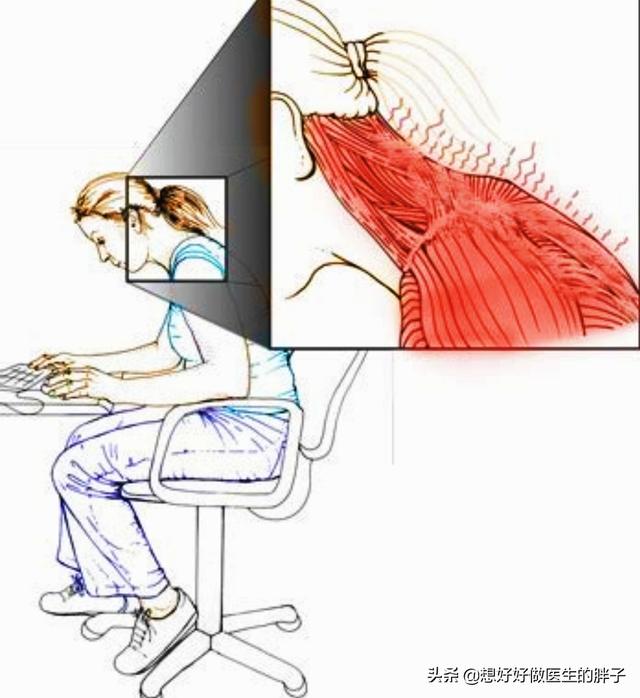

1) Première raison :C'est le plus courant.À l'heure actuelle, de nombreuses personnes doivent travailler pendant une longue période en raison d'un travail sédentaire, face à l'ordinateur ou à l'ordinateur de bureau.céderUtilisez votre téléphone portable comme indiqué ci-dessous :

Je suis sûr que chacun d'entre vous s'étonnera de voir une telle posture, n'est-ce pas ce que nous faisons tous les jours, et c'est la véritable cause de la douleur dans les angles internes et supérieurs de l'omoplate. Nous pouvons approfondir ce sujetMécanismes à l'origine des lésionsDans cette position, il y a un muscle important qui stabilise la colonne cervicale.

Comme indiqué ci-dessus, ce muscle est anatomiquement ce que l'on appelle un "levator scapulae (anatomie)". Il se développe d'une part sur l'apophyse transverse des vertèbres cervicales 1 à 4, et d'autre part à l'endroit même où se trouve le point douloureux (l'angle supérieur interne de l'omoplate). Sa fonction principale est la suivante :Lorsque la fin du point de douleur est fixéeLa tête et le cou sont inclinés vers l'arrière lorsque les deux côtés sont contractés et raccourcis.Lorsque la tête est baissée pendant une longue période, elle s'étire progressivement lorsque la tête est tirée vers l'avant, jusqu'à ce qu'à la limite, lorsqu'il n'est plus possible de l'étirer davantage, il y ait une douleur à l'angle supérieur interne de l'omoplate, à l'extrémité stationnaire.。